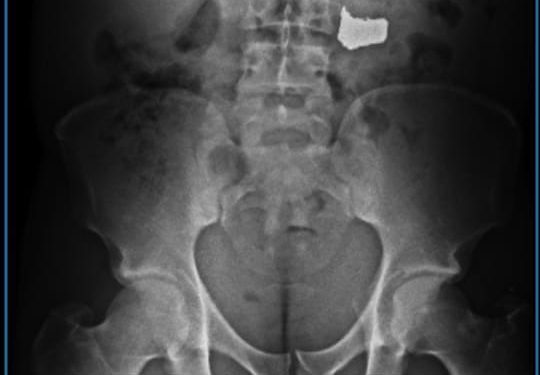

Guarnições da 11ª CIPM encaminharam o suspeito para a Unidade de Pronto Atendimento (UPA) dos Barris. Os médicos realizaram um exame de Raio X e atestaram a presença da corrente. Após ser liberado da unidade de saúde, o criminoso foi apresentado na Central de Flagrantes.